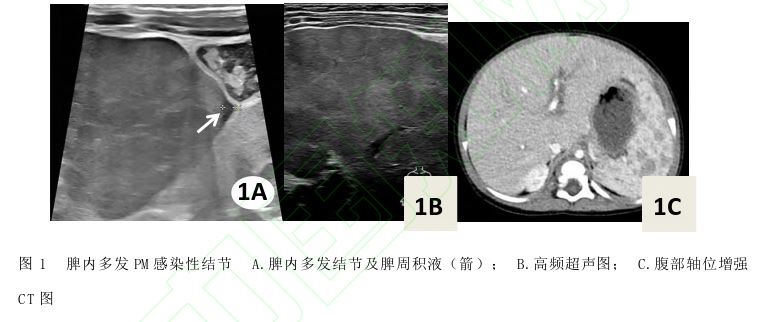

;脾内实质回声分布不均匀、脾周积液 (图1A);高频线阵探头 (7~15 MHz)扫查见脾实质回声不均匀,内见多发低回声结节状改变,边界欠清晰,形态尚规则,内部回声欠均匀 (图1B);CDFI于脾低回声结节内未见明显血流信号。腹部增强CT:肝脏增大,Glisson鞘水肿,肝下缘少许积液;脾大,脾脏多发低强化灶 (图1C)。病原学检查示马尔尼菲青霉菌 (Penincillium Marneffei, PM)阳性、HIV阴性。临床综合诊断:HIV阴性PM感染。本例报道经医院伦理委员会批准(2025-16)。

、体重下降、肝脾大、淋巴结肿大及多器官受累;超声主要表现为肝脾大、实质回声不均匀伴多发低回声结节及淋巴结肿大。本例为播散型PM感染,腹部常规超声见肝大、Glisson鞘水肿;脾大、实质回声分布不均匀;而高频超声清晰显示脾内多发的低回声结节,提示高频超声有助于提高病变检出能力。鉴别诊断:①淋巴瘤